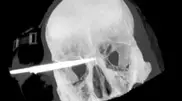

Житель Сальвадора прожил 18 лет с лезвием ножа в голове Житель Сальвадора прожил 18 лет с лезвием ножа в голове Сапожник из Сальвадора подвергся нападению в 1995 году. Но до 2007 года он не подозревал, что в его черепе осталась часть лезвия размером в 9 сантиметров.

22 марта 2013 10:08